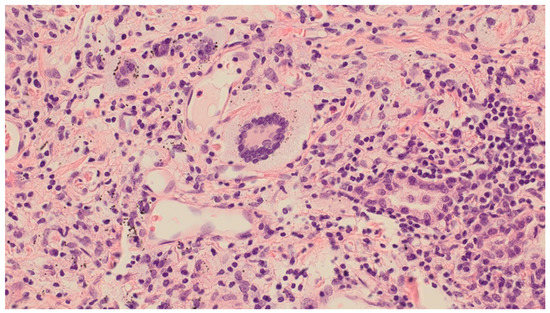

Uncommon Presentation of Granulomatosis with Polyangiitis Mimicking Metastatic Lung Cancer